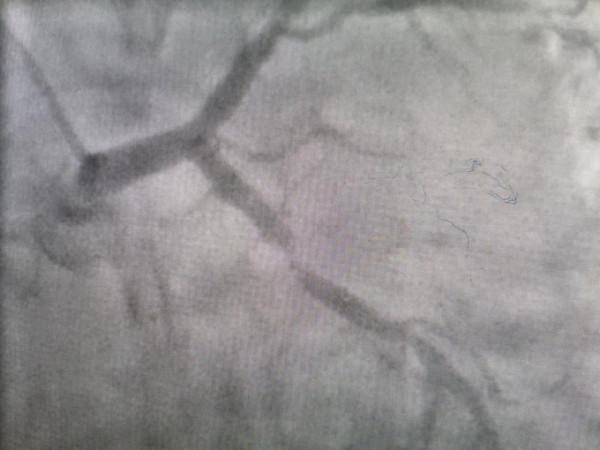

每次發作時心電圖心電圖有些改變但變化不大,做磁共振時心電圖變化最大。綜合考慮還是冠心病發作引起的 無論怎樣,患者症狀重,還是再次造影吧

這個狹窄程度是需要處理的,無論和症狀是否有關!況且查無他因。